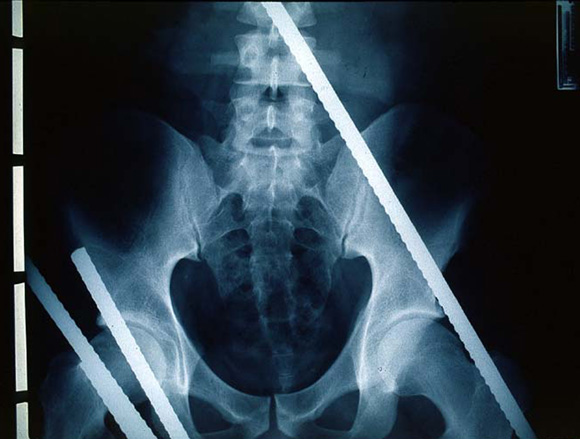

During the extrication process, the patient was covered with a blanket and supported from the back (Figure A). Within 53 minutes of the fall, the patient was admitted to the emergency department. Abdominal x-ray indicated that two rods had entered the abdominal cavity (Figure B). Surgical investigation revealed, in addition to laceration of the right femoral artery, major trauma to the abdomen (perforated rectum, jejunum and duodenum, incomplete rupture of the spleen, and injury to the head of the pancreas). The patient recovered from severe infection of the abdominal cavity with concomitant septicaemia, and was discharged from hospital three months later.